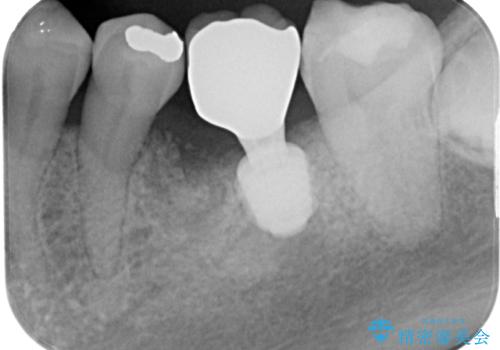

下顎大臼歯の抜歯即時埋入インプラント治療では、複数ある歯根のうち、後方の歯根部にインプラントを埋入することで一般的であり、今回破折して骨吸収が著しいのは前方の歯根であったため、事前に仮歯を用意した上で、抜歯即時埋入インプラントによる補綴治療を行うこととしました。

来院されるまではインプラント治療を躊躇されていましたが、抜歯即時埋入により、単回の外科処置で治療が終えられることのメリットを理解され、インプラントによる補綴治療を行いました。